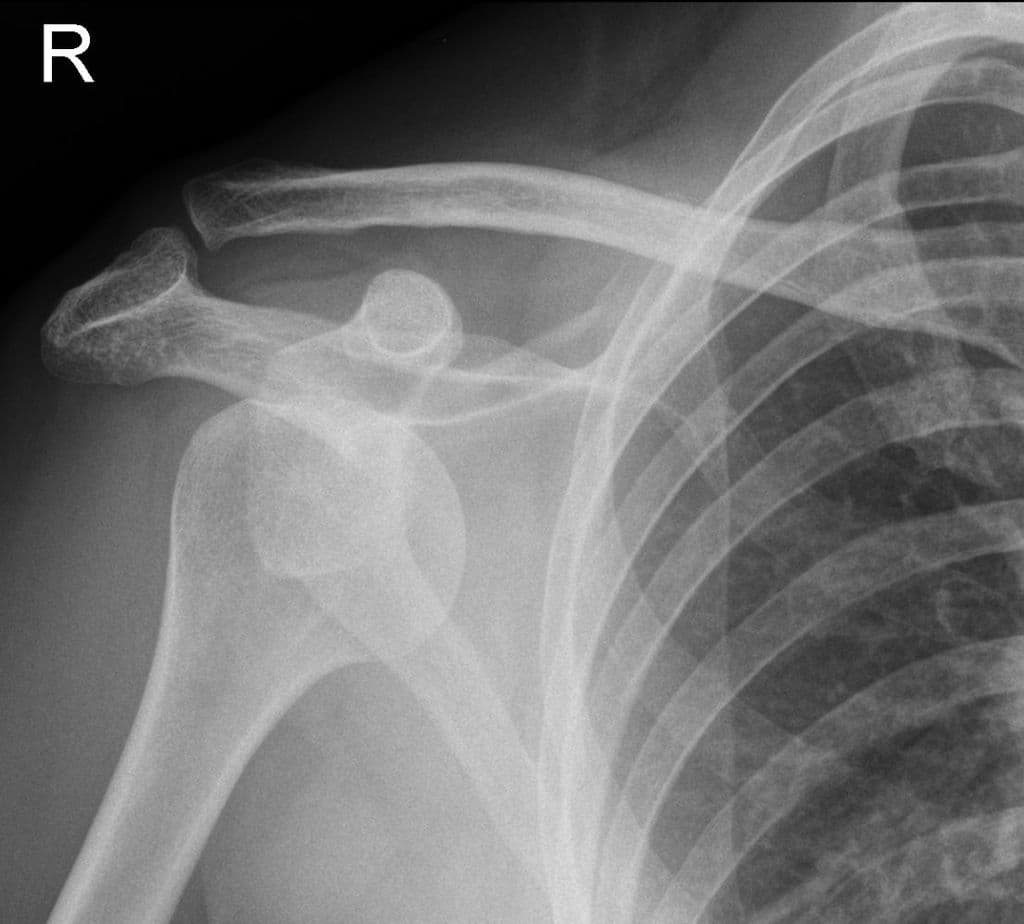

Trật khớp ra trước và xuống dưới thường là những chẩn đoán đơn giản, với chỏm xương cánh tay (humeral head) và đường viền của ổ chảo (glenoid) không khớp nhau (incongruent).

Khi chỏm xương cánh tay bị di lệch vào trong và nằm chồng lên ổ chảo, đó là trật khớp ra trước.

Trật khớp ra sau có thể khó nhận diện chỉ trên phim thẳng AP (như có thể gặp trong bối cảnh khảo sát thứ cấp của một chấn thương), vì chỏm xương cánh tay di chuyển trực tiếp ra sau và sự tương quan khớp có vẻ như vẫn được duy trì (ít nhất là khi nhìn thoáng qua).

Tất cả các trường hợp trật khớp nên được nhận diện dễ dàng trên thế chữ Y xuyên bả vai (trans-scapular Y views). Khi chỏm xương cánh tay nằm đúng vị trí, nó sẽ chiếu vào trung tâm của chữ Y được tạo bởi mỏm quạ (coracoid), bản xương bả vai (blade of the scapula) và gai vai (spine of the scapula) (mỏm cùng vai - acromion).